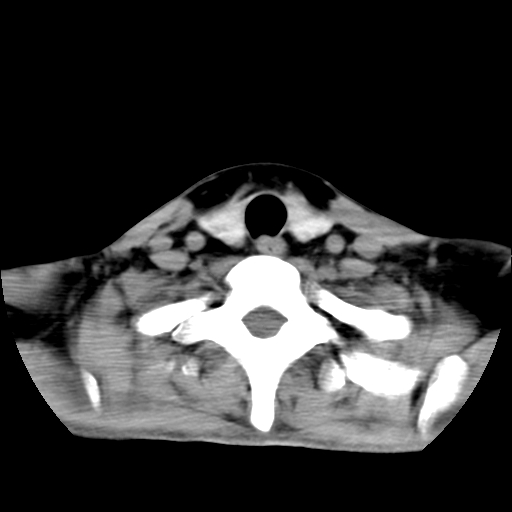

标题: CT24019:男,45岁,发现颈部肿物5个月。 [打印本页]

男,45岁,发现颈部肿物5个月,彩超示:双侧颈部及下颌部软组织增厚。

考虑双侧颈项部良性对称性脂肪增多症。